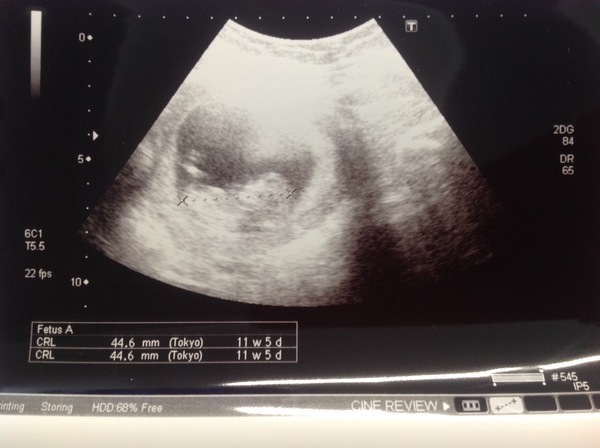

Just to update myself, I'm 31 pg with baby no.3 (dd7 and ds4) and edd 16th Feb! Got my 12 week scan 2 weeks on Friday and a little nervous/excited !!